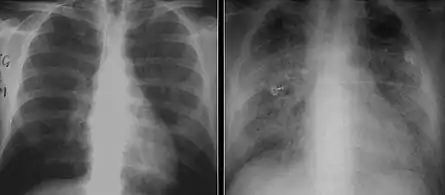

The diagnosis can be confirmed by the characteristic appearance of the chest X-ray and an arterial oxygen level (PaO2) that is strikingly lower than would be expected from symptoms. Gallium 67 scans are also useful in the diagnosis. They are abnormal in about 90% of cases and are often positive before the chest X-ray becomes abnormal. Chest X-ray typically shows widespread pulmonary infiltrates. CT scan may show pulmonary cysts (not to be confused with the cyst-forms of the pathogen).

These chest radiographs are of two patients. Both show ground glass opacities. The left X-ray shows a much more subtle ground-glass appearance while the right X-ray shows a much more gross ground-glass appearance mimicking pulmonary edema.[7]